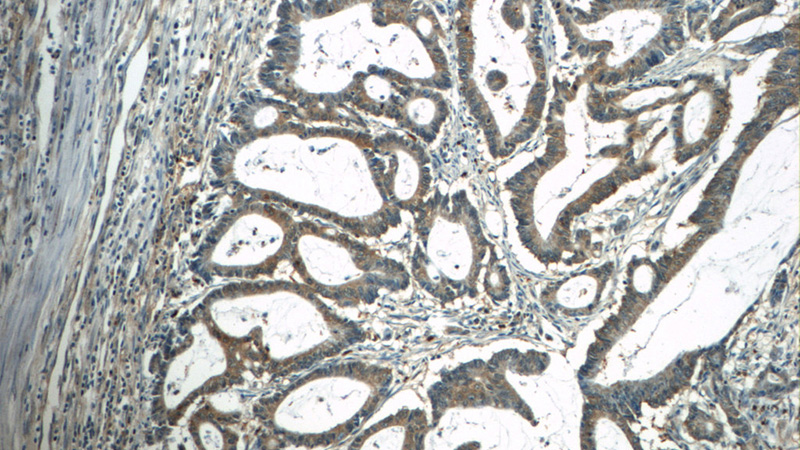

Immunohistochemistry of paraffin-embedded human colon cancer tissue slide using Catalog No:108844(CAPZA1 Antibody) at dilution of 1:50 (under 10x lens)